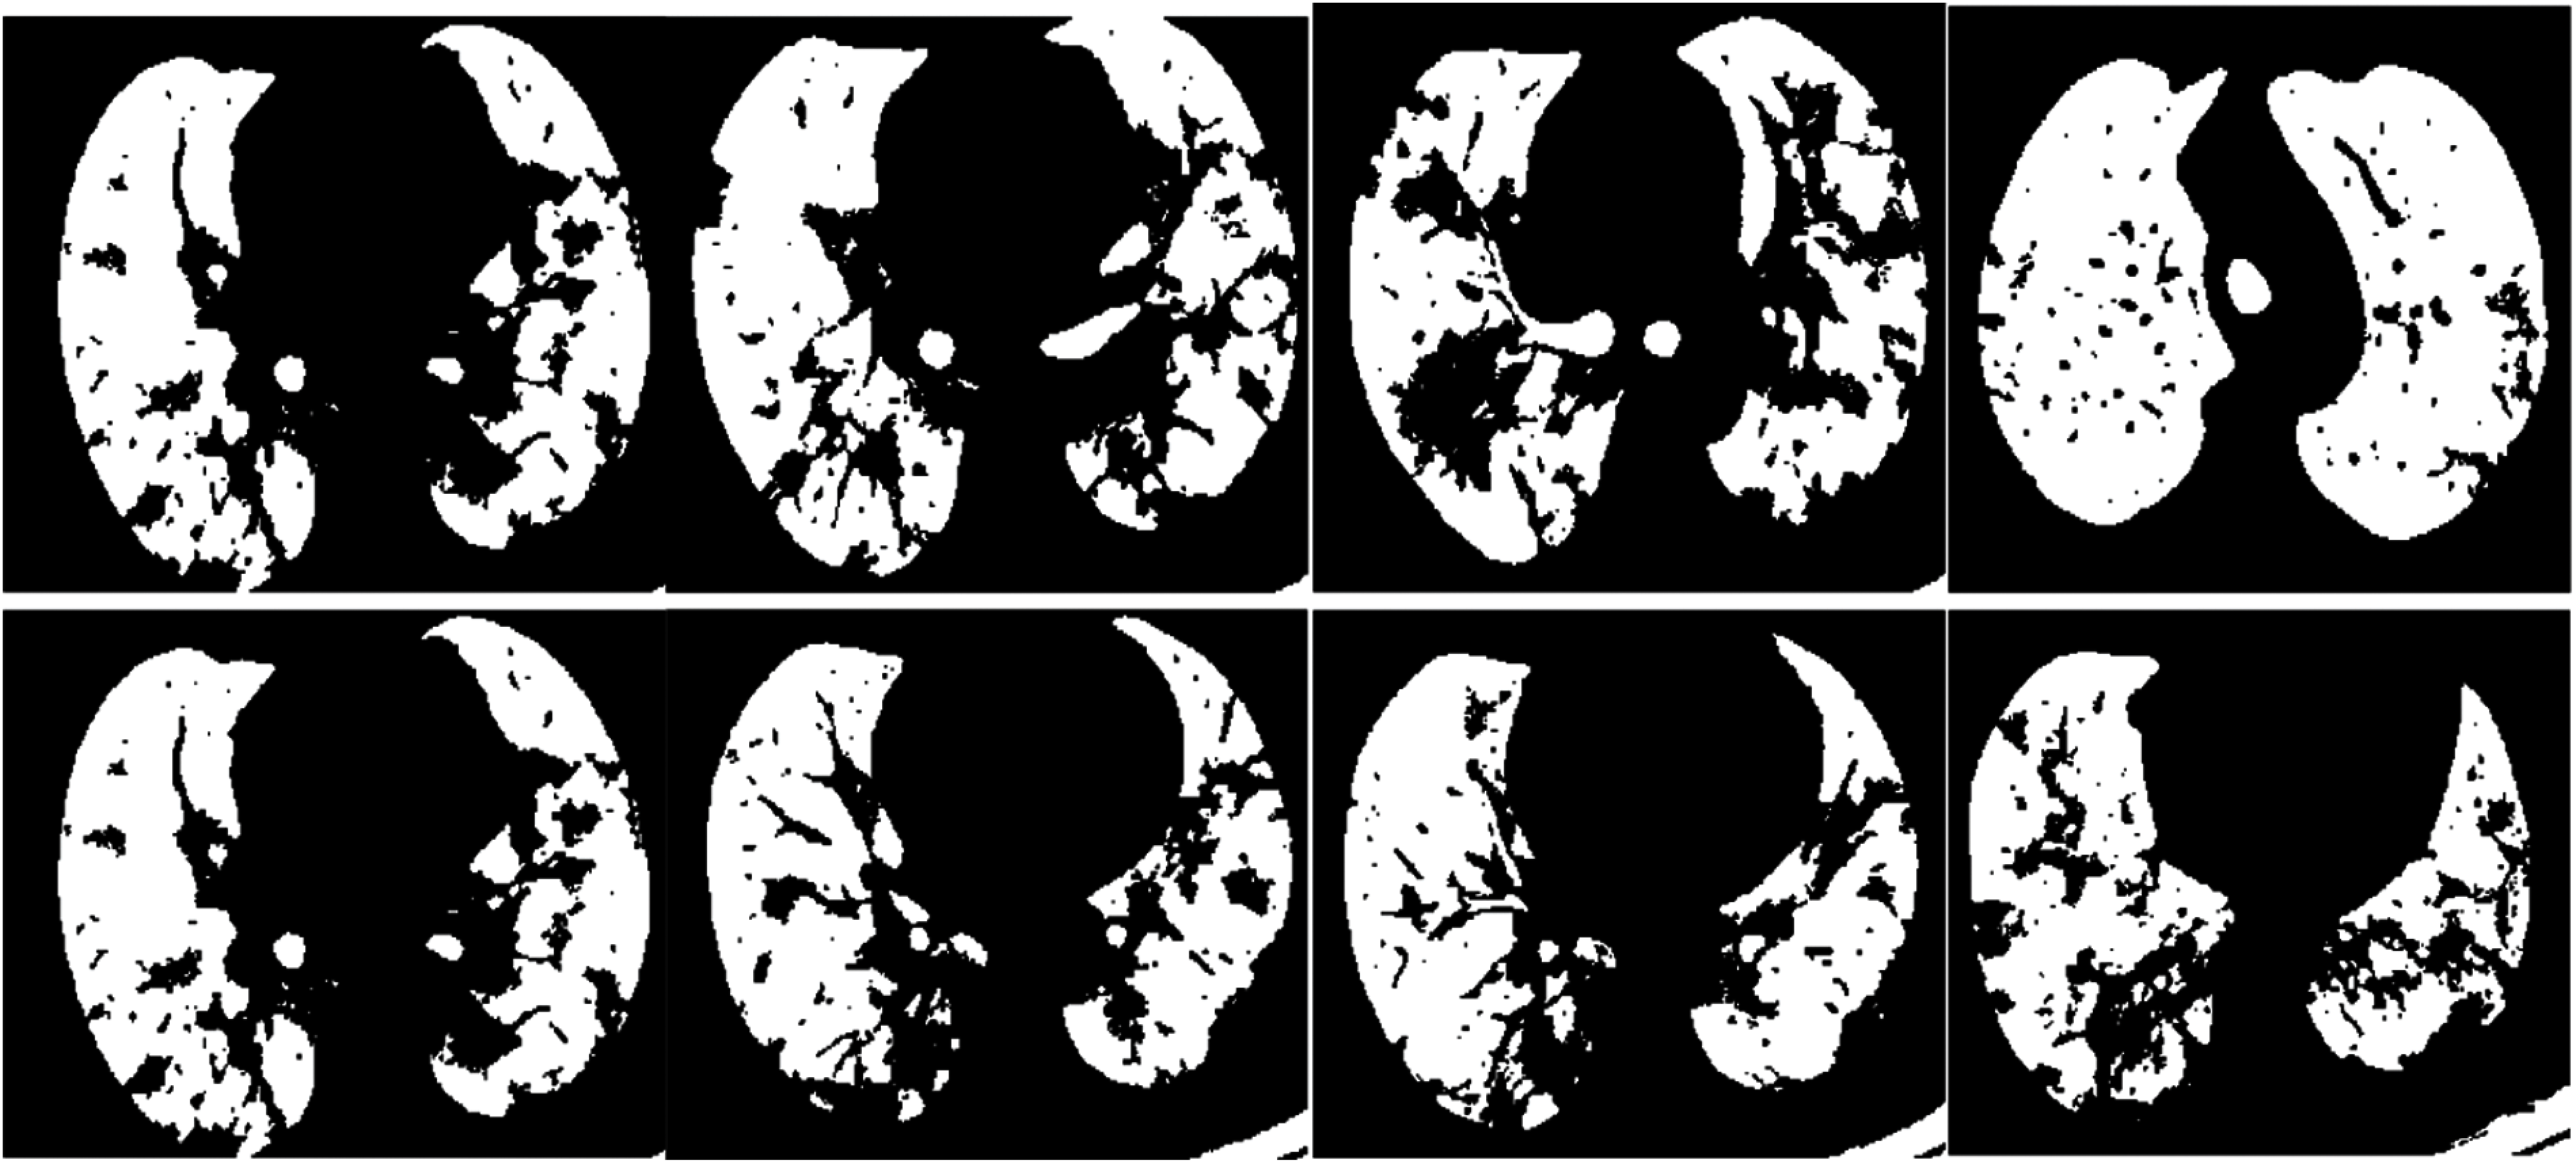

The proposed SPCNN-based segmentation approach is employed after applying the classification process. Pneumonia and COVID-19 images are segmented to identify the area of interest, precisely. The main objective of this segmentation stage is to assist the specialists in diagnosing the disease in an automated manner and discovering the proper therapy for COVID-19 cases. Figs. 9 and 10 clarify samples of segmented pneumonia and COVID-19 CT images, respectively. Tabs. 4 and 5 show the obtained accuracy, precision, sensitivity, F1 score, DICE, MCC, specificity, and Jaccard [28,29] assessment metrics of the proposed SPCNN-based segmentation approach for pneumonia and COVID-19 CT images. The obtained visual results reveal the high difference between pneumonia and COVID-19 cases in segmented CT images. Additionally, the attained values of the assessment metrics of the segmented CT images confirm the high efficiency and accuracy of the proposed SPCNN-based segmentation approach as presented in Tabs. 4 and 5.

Figure 9: Samples of the resulting segmented pneumonia images

Figure 10: Samples of the resulting segmented COVID-19 images